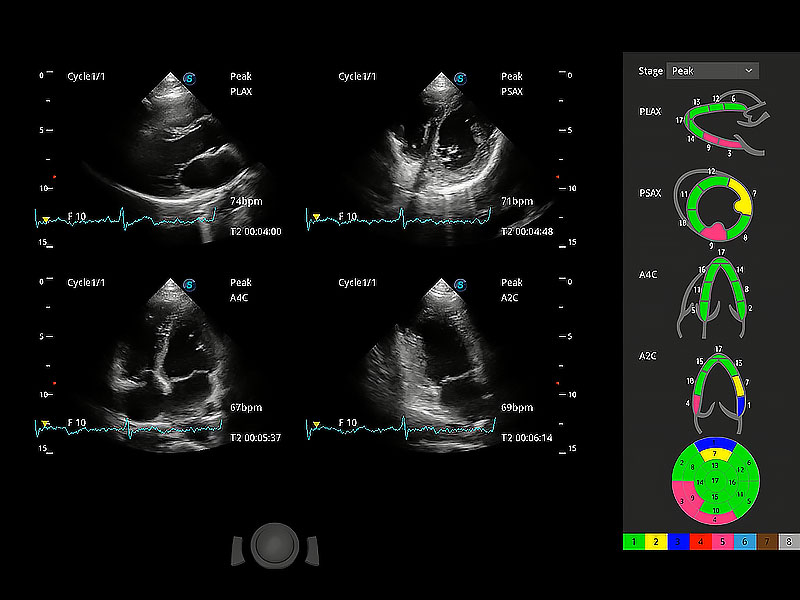

具备多种协议可选,同时支持17阶段划分法和专业的SE报告。